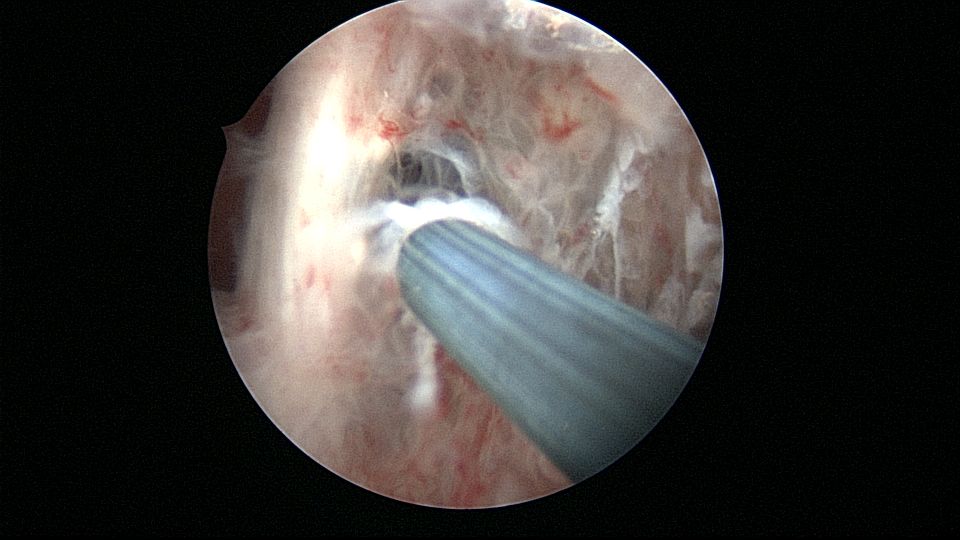

患者25岁,G1P0,停经52天,稽留流产,B超宫内偏右查见大小约2.4cmx1.0cmx1.7cm孕囊回声,形态规则,内可见直径约0.4cm的卵黄囊回声,未见胎芽,孕囊旁肌层最薄处厚约0.5cm,子宫中下段回声连续性欠佳,似可见一分隔回声。2021年7月宫腔镜探查,胚胎着床于宫腔前壁偏右,宫颈内口及宫腔左侧壁粘连。清除妊娠组织,单极电针分粘,恢复宫腔形态,双侧输卵管开口显露(第一次怀孕,宫腔粘连原因?)。2022年7月自然妊娠,2023年3月足月剖宫产分娩。2024年12月,外院人流术后1+月,宫内残留,与后壁肌层分界欠清,局部血流信号增多,到我院宫腔镜切除残留组织(后3张图片)。现患者30岁,G3P1。宫腔粘连常常不能阻止妊娠,但胚胎停育发生率增加。